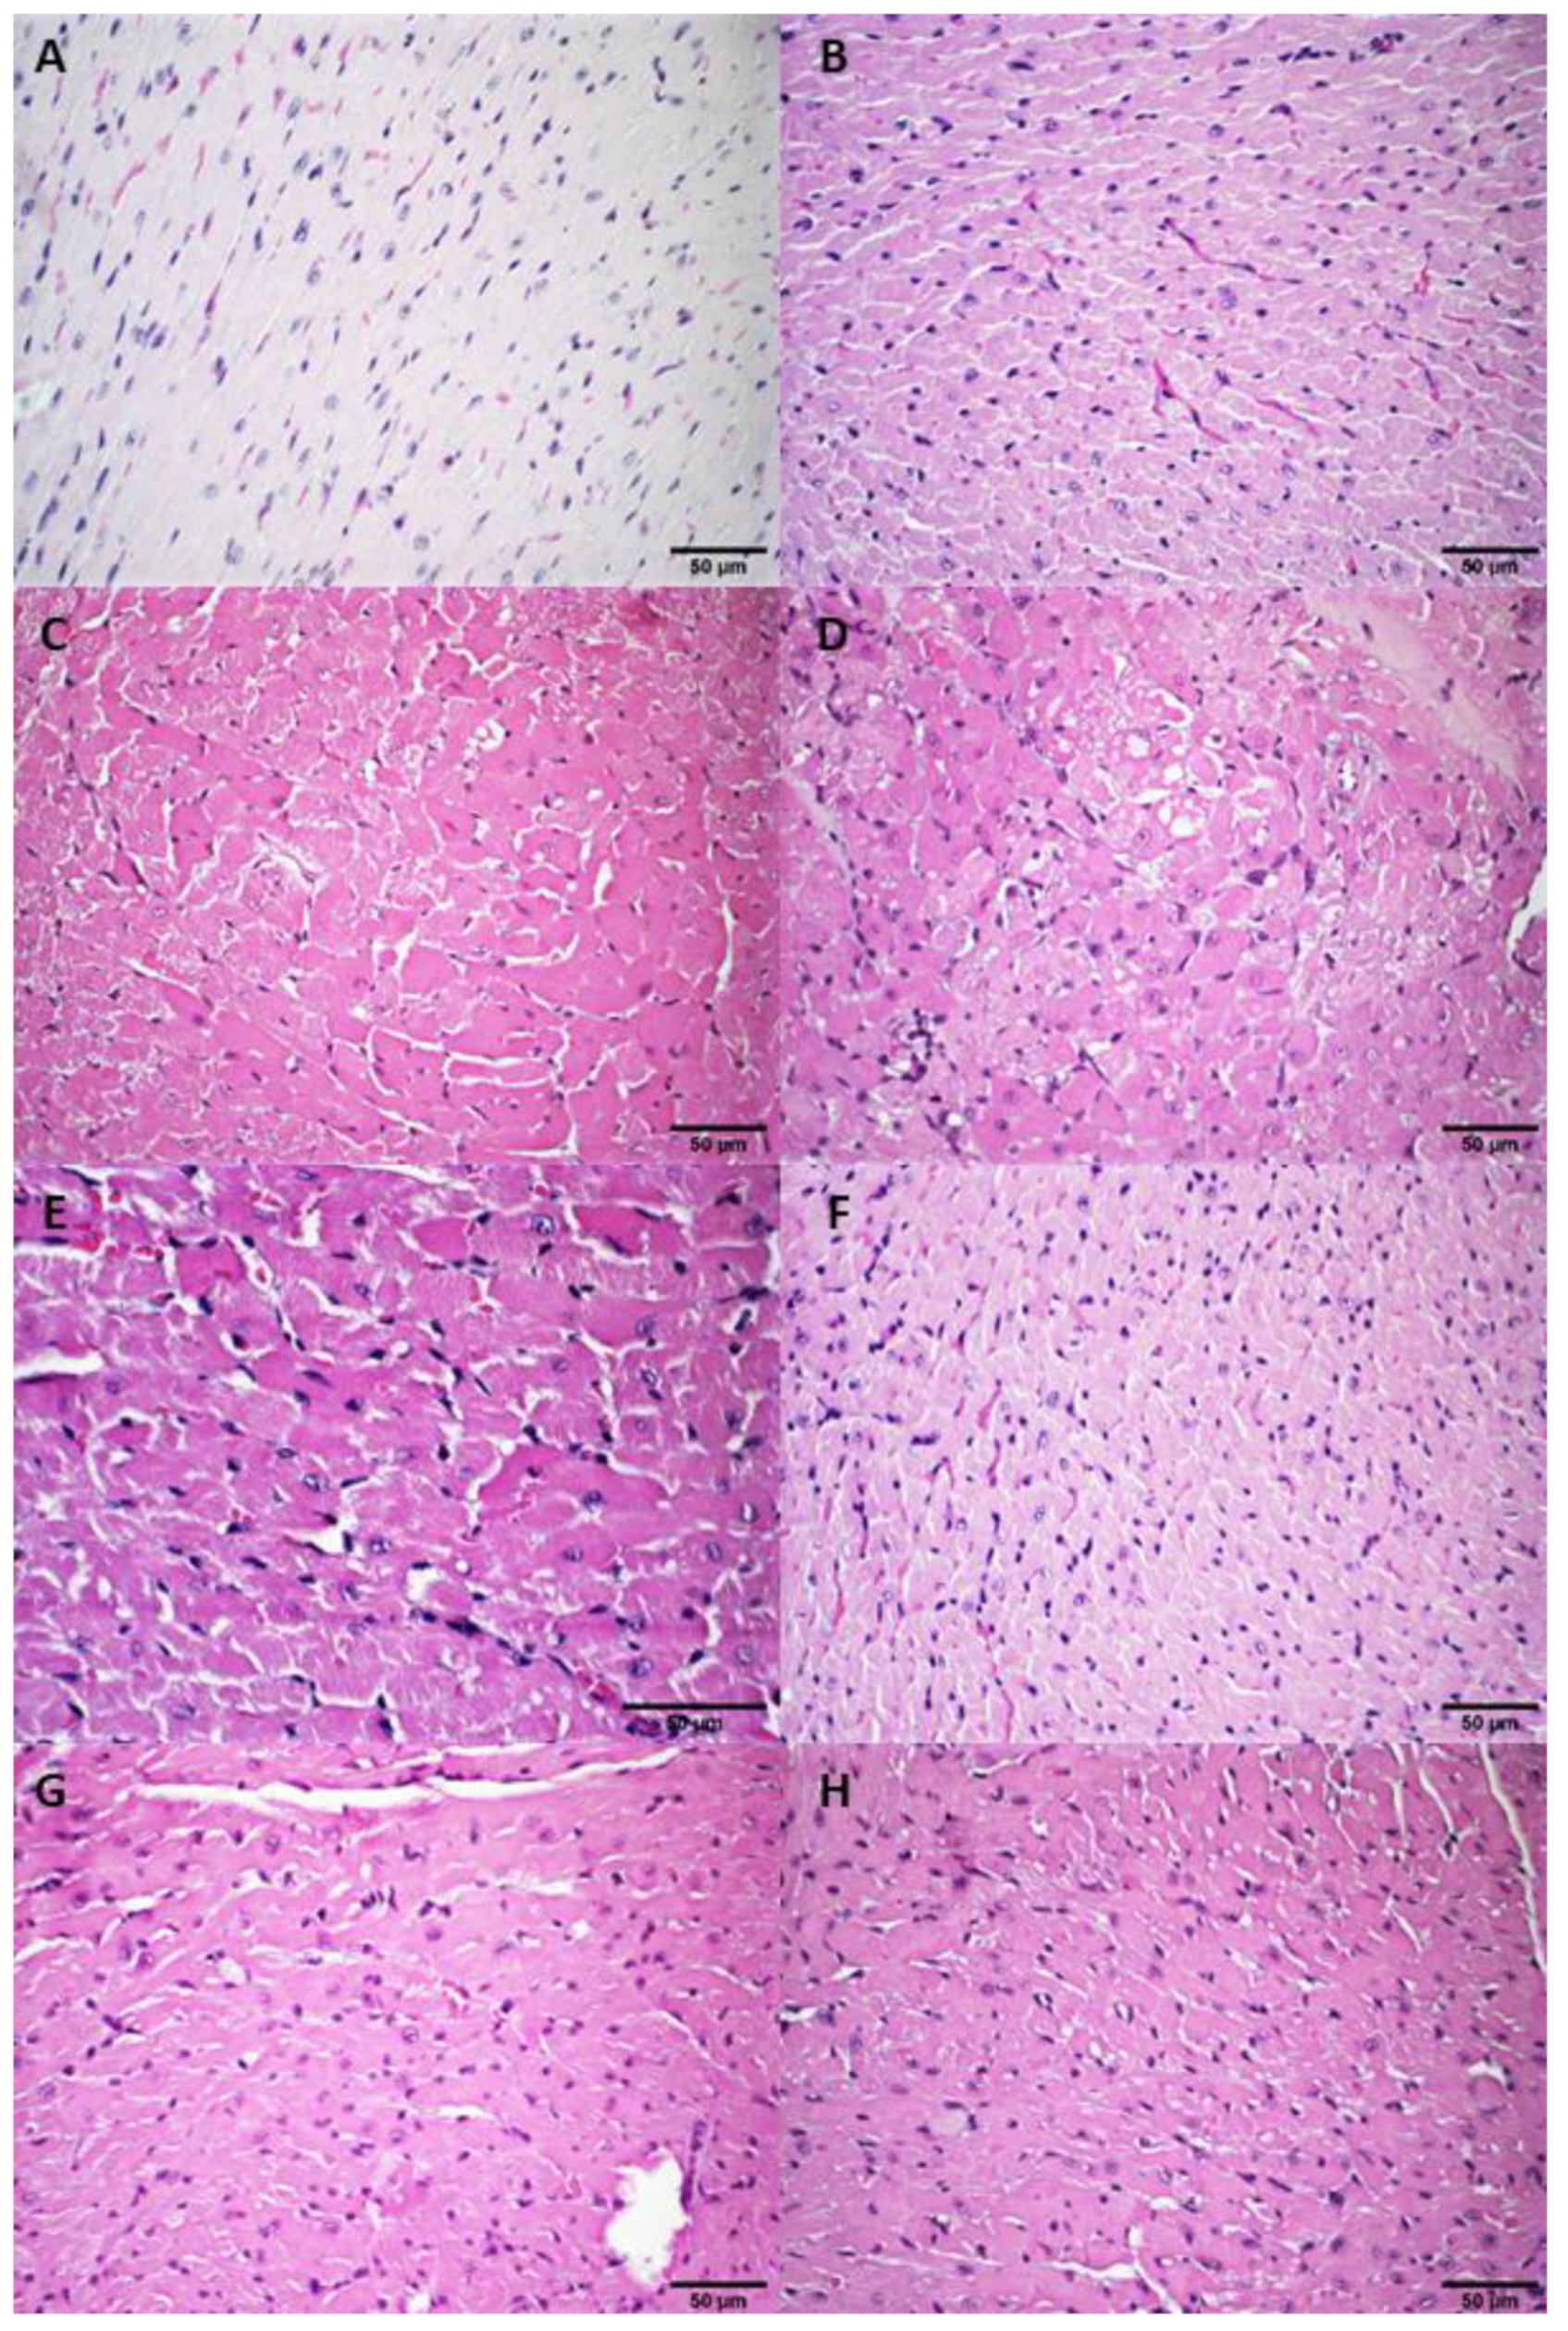

3.2.4. Histological Analysis

3.3.2. Histological Analysis